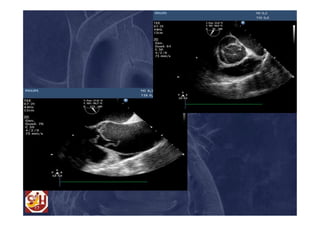

Two-step approach Clinical Case 2 • 57 yo man; • Pain, syncope and 3 h transient drowsiness (no neurological damages); • TTE: severe IA, without pericardial effusion; • CT scan: full rupture (tear) in sino-tubular junction and absence of malperfusion.